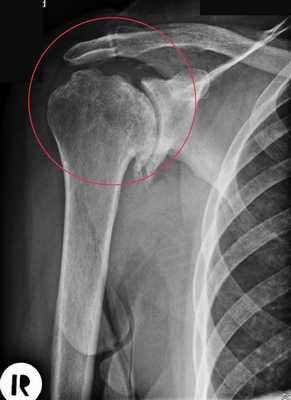

Рентгенография для обнаружения костных наростов, сужения суставной щели и других деформаций.

Выделяют 3 стадии остеоартроза плечевого сустава. Для каждой характерны свои симптомы и рентгенографические признаки. Но многие медики пользуются классификацией, разработанной Kellgren и Lawrence. Она описывает 4 этапа развития этого дегенеративно-дистрофического заболевания.

На рентгенографических снимках заметно нечетное сужение суставной щели, приводящее к уменьшению подвижности плеча. На этой стадии появляются единичные остеофиты на краях суставных плоскостей. Возникают и первые болезненные ощущения после подъема тяжестей, выполнения монотонных движений, переохлаждения.

При остеоартрозе плеча 3 степени тяжести интенсивность болезненности усиливается, снижается объем движений, а при сгибании или разгибании сустава, отведении руки за спину отчетливо слышатся щелчки. На рентгенограммах обнаруживаются множественные костные наросты, субхондральный остеосклероз, заметное сужение суставной щели.

На этой стадии сустав сильно деформирован, а его подвижность резко ограничена. Суставная щель практически полностью отсутствует. На снимках отчетливо визуализируются субхондральные кисты (полости с полужидким содержимым), обширные остеофиты. При заболевании 4 степени в суставе свободно перемещаются кусочки разрушенного хряща. Если они попадают между костными поверхностями, то образуется суставная «мышь», а плечо блокируется.

Выявление патологии

Наиболее информативна при остеоартрозе плечевого сустава рентгенография. По характерным рентгенографическим признакам можно выявить не только само заболевание, но и его стадию и особенности течения. При подозрении на воспаление тканей, а также для более детального изучения состояния сустава проводится МРТ, КТ. Выполнение артроскопии позволяет сделать прицельный забор биологических образцов:

Деформирующий артроз плечевого сустава 1 степени на рентгенограмме практически незаметен. Иногда удается установить небольшое сужение суставной щели. Однако при более серьезном обследовании – КТ или МРТ, поражение костно-хрящевой структуры четко заметно. Видны начальные деформации суставных поверхностей, отек подлежащих мягких тканей, небольшая узурация.

Деформирующий артроз плечевого сустава 2 степени проявляется уже значительными изменениями. Их можно представить так: